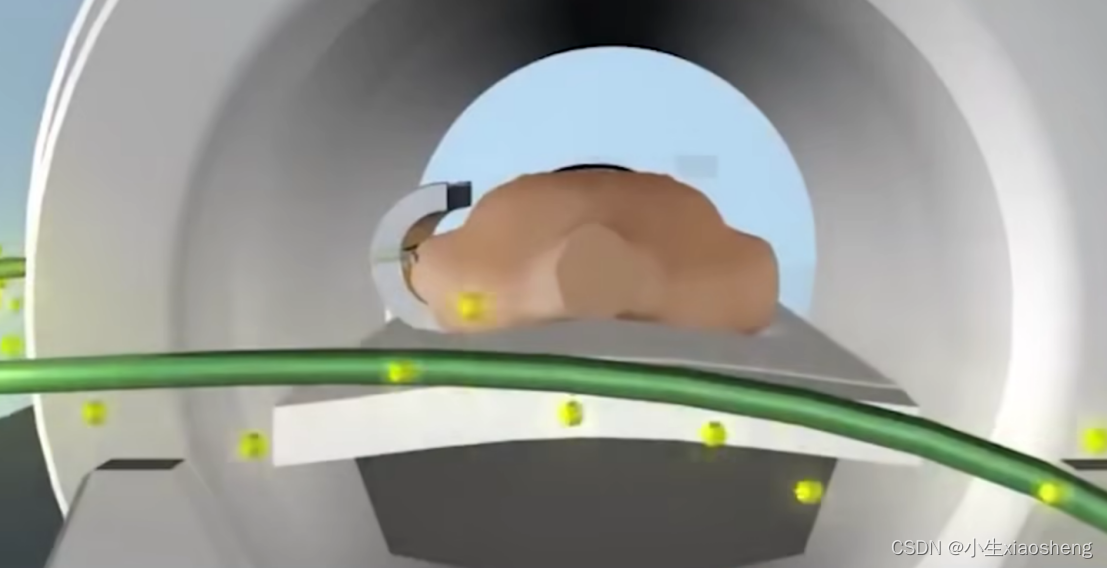

CT:X光的升级版本,原理是一样的,它是三维的,要把检查的器官切成一层一层的,与X光生成一张图片不同,CT是射线从不同角方向射入人体而产生大量平面图片,所以拍的时候不能动,再结合计算机生成立体图像,适合比如肺、心脏、血管。